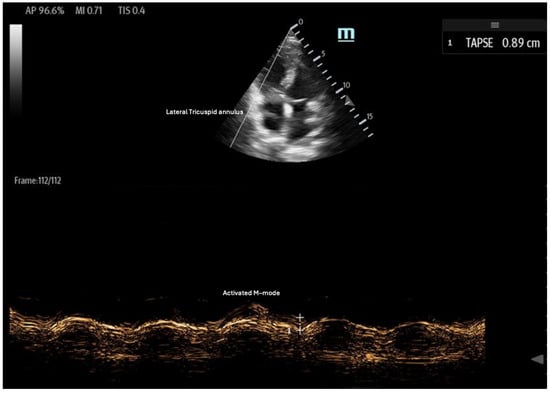

- Tricuspid annular plane systolic excursion (TAPSE): TAPSE is a simple and widely used measure of RV systolic function, assessed using the M-mode of the 2D ultrasound in the apical four-chamber view (Figure 6). It quantifies the displacement of the tricuspid lateral annulus towards the cardiac apex during systole, reflecting the RV’s longitudinal contraction [35]. Greater displacement indicates better RV contractility, while a TAPSE < 17 mm is indicative of RV systolic dysfunction, with high specificity and low sensitivity [35,36,37]. TAPSE is advantageous due to its ease of measurement; however, it is limited by its two-dimensional (2D) interpretation of a 3D structure. Additionally, its accuracy can be affected by ultrasound probe positioning and increased RV afterload [36].

Figure 6. Tricuspid annular plane systolic excursion (TAPSE): apical 4-chamber view with M-mode activation, demonstrating reduced TAPSE (measured at the bottom 2D M-mode). - Right ventricular outflow tract velocity–time integral (RVOT-VTI): RV contractility can be evaluated using the RVOT-VTI, which represents the distance traveled by blood across the RVOT during systole. Stroke volume is calculated by multiplying the RVOT cross-sectional area by the RVOT-VTI. This measurement provides insight into both RV function and pulmonary vascular resistance, with an RVOT-VTI ≥ 12 cm considered normal [38] (Figure 7). The RVOT VTI is a better predictor of RV dysfunction in cardiogenic shock states compared to TAPSE and may also have prognostic value in patients with pulmonary hypertension [39,40].